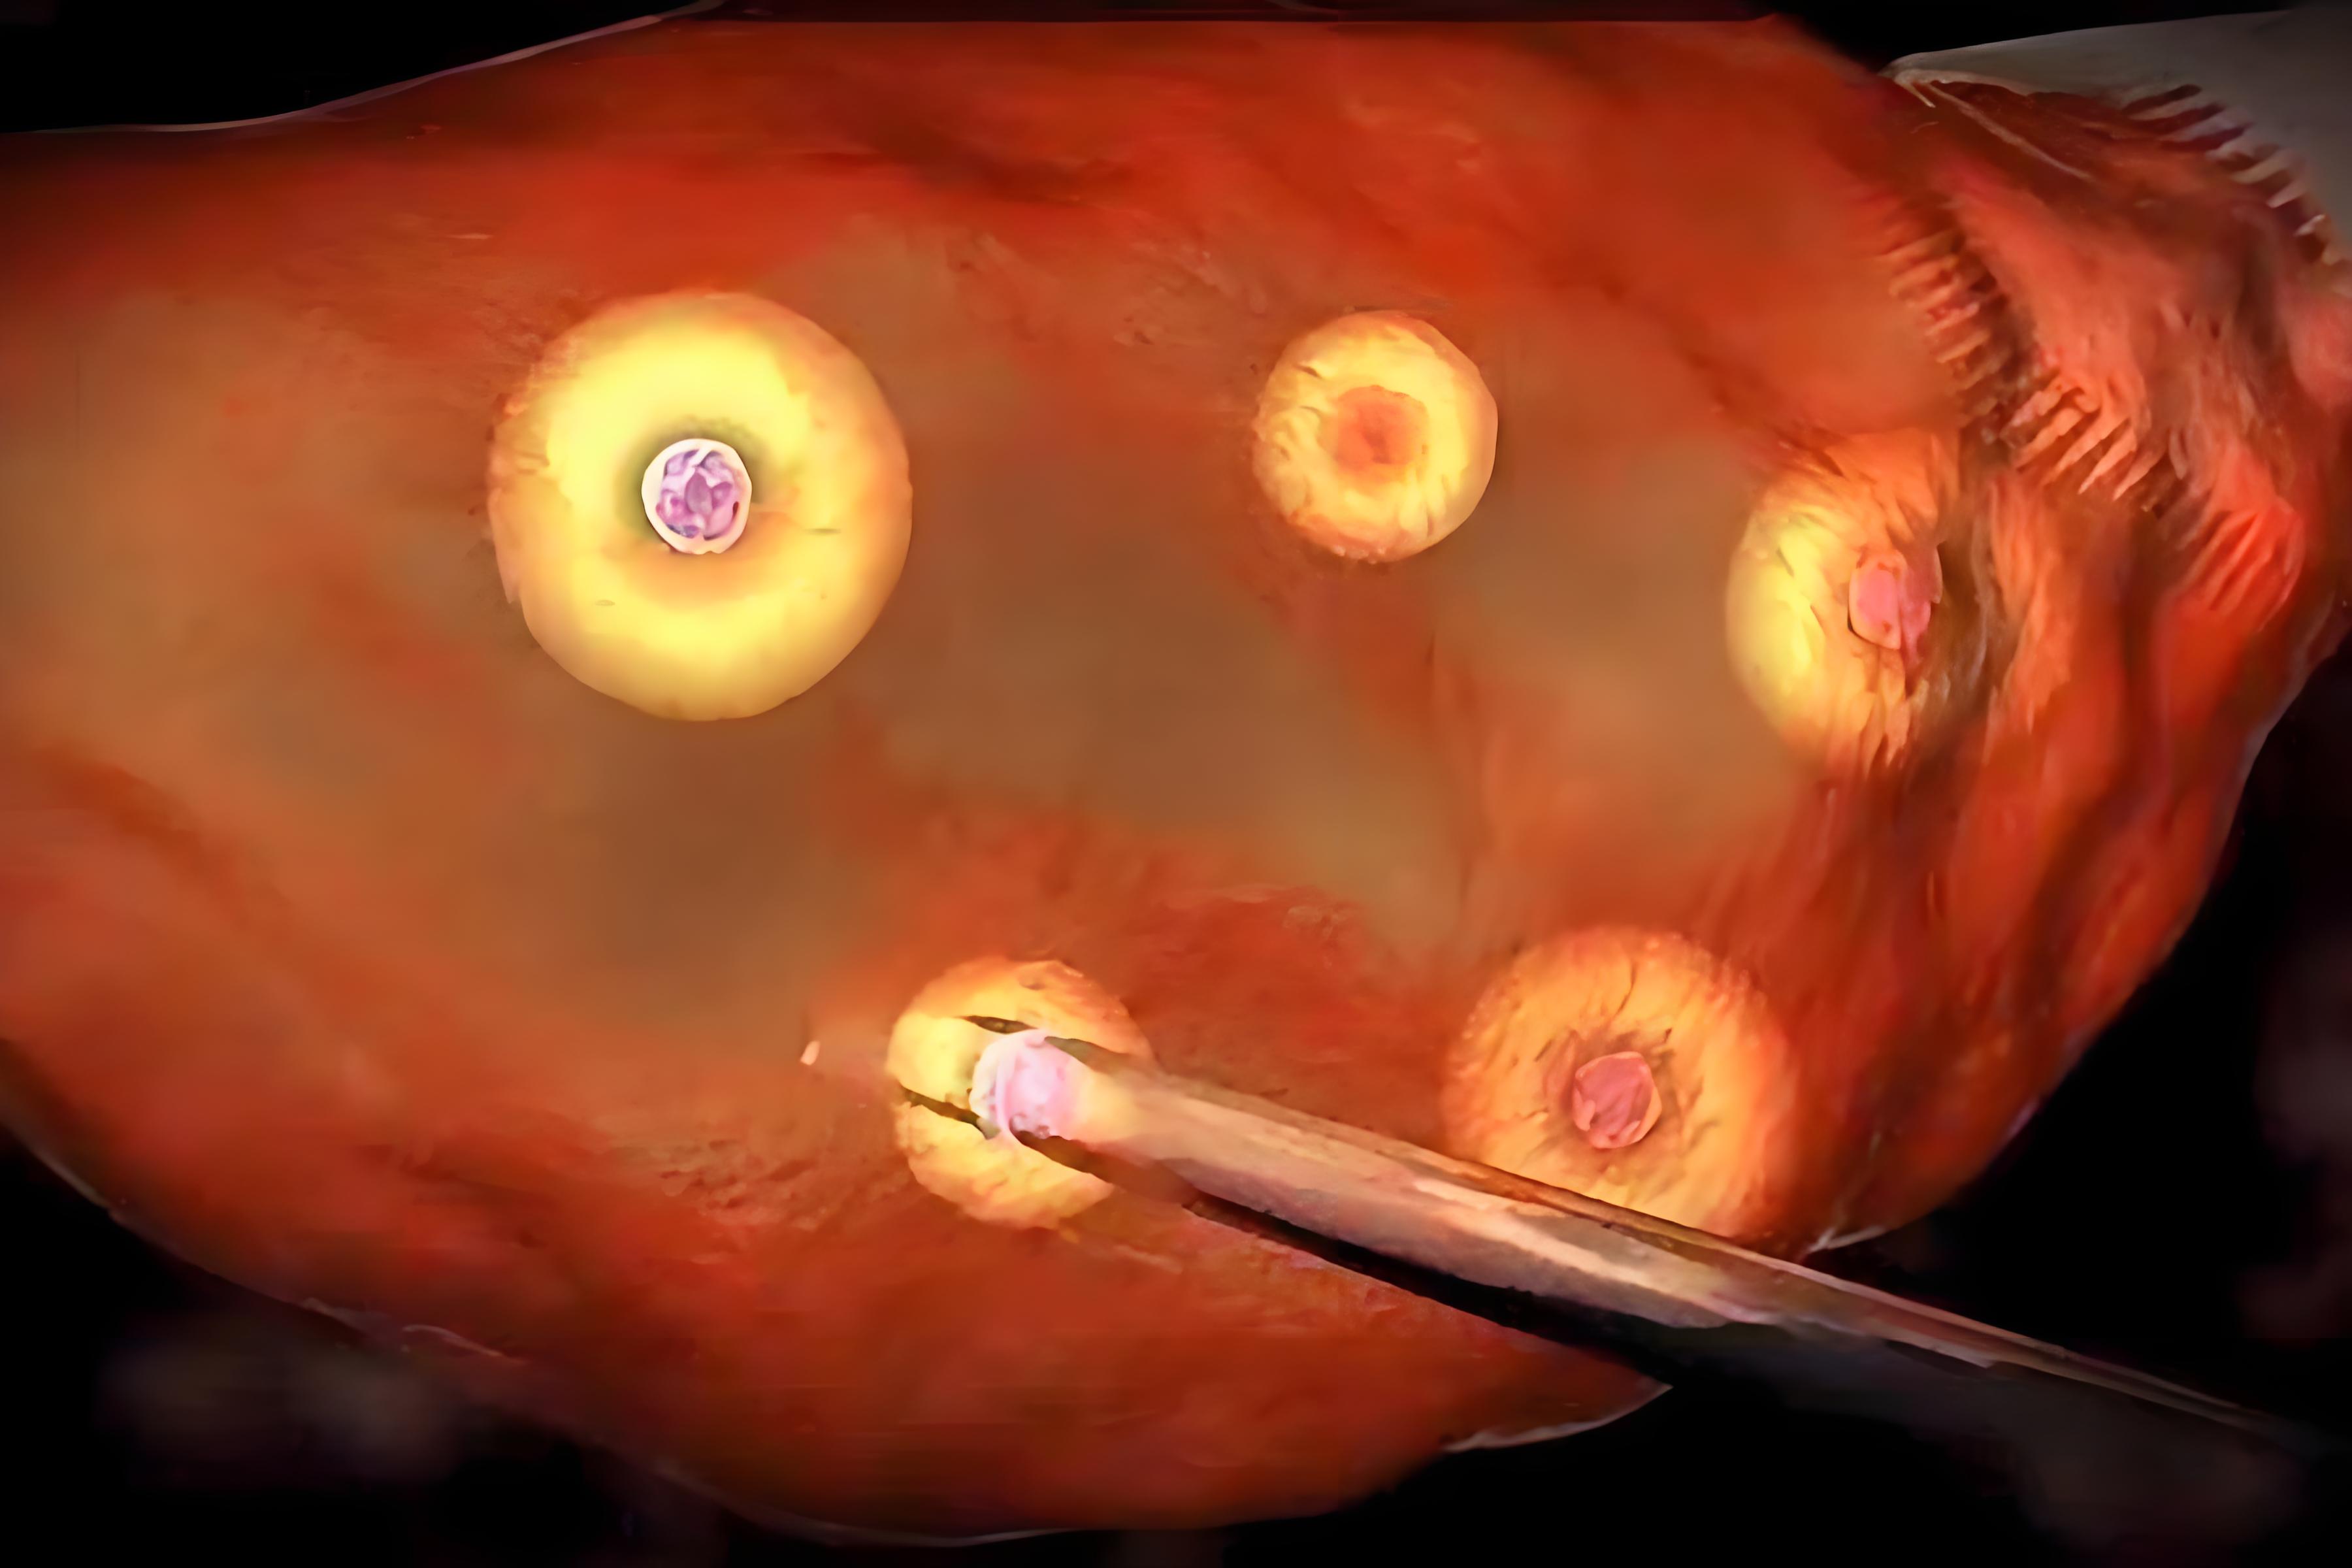

2.取卵相关风险

取卵虽为微创操作,但仍存在潜在风险,包括盆腔出血、盆腔感染、邻近脏器损伤以及麻醉相关不良反应。规范的术前评估与严格的无菌操作可显著降低上述风险的发生率。

3.单胚胎移植策略的普及

该策略的实施依赖于两个技术前提:一是囊胚培养技术,可将发育潜能较高的胚胎筛选至囊胚阶段;二是胚胎植入前遗传学检测技术,可进一步筛选出染色体正常的整倍体胚胎。在确认胚胎质量优良的前提下,移植一枚健康囊胚的妊娠率与移植两枚胚胎相当,而多胎妊娠风险则被降低。

4.胚胎遗传学风险的筛查

PGT技术通过对囊胚滋养层细胞进行活检,分析胚胎的染色体数目、结构及单基因病致病位点。筛选出的整倍体胚胎具有更高的着床潜力和更低的流产风险。对于有遗传病家族史的夫妇,PGT技术还可有效阻断致病基因的代际传递。